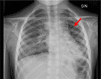

Case presentation: We herein report the case of a 7-year-old Caucasian girl who was admitted to the Rheumatology Department with a history of febrile chough and polyarthritis which led initially to the suspicion of an autoinflammatory disease. She had overt polyarthritis with knees deformities and presented with severe pneumonia. A chest Computed Tomography (CT) scan showed bilateral bronchiectasis, parenchymal consolidation and interstitial lung disease; rheumatoid factor and type I interferon signature resulted negative, therefore excluding COatomer Protein subunit Alpha (COPA) syndrome. A diagnosis of sarcoidosis had been suspected based on histological evidence of granulomatous liver inflammation, but ruled out after detecting normal angiotensin converting enzyme and chitotriosidase blood levels. Based on her past medical history characterized by at least six episodes of pneumonia in the previous 4 years, immunological phenotyping was performed. This showed complete IgA and IgE deficiency with defective antigen-specific antibodies to Pneumococcal, Tetanus toxin and Hemophilus Influenzae B vaccines. Additionally, low numbers of B cells and recent thymic emigrants (RTE) were found (CD4Ra 1.4%), along with a low CD4+/CD8 + T cells ratio (< 1). Finally, based on gait disturbances (wobbly wide-based walking), serum alfa-fetoprotein was dosed, which resulted increased at 276 ng/ml (normal value < 7 ng/ml). A diagnosis of Ataxia-Telangiectasia was made, strengthened by the presence of bulbar telangiectasia, and then confirmed by Whole Exome Sequencing (WES).